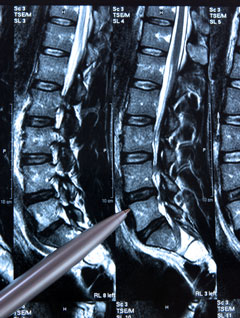

Lors du contrôle de densitométrie, une VFA est réalisée, dont vous trouverez les images :